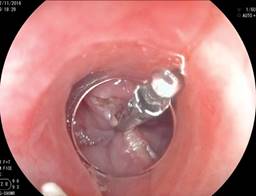

En los primeros 10 pacientes una vez identificada la luz del esófago, se introdujo una guía metálica a la cavidad gástrica y sobre ésta un dilatador de Savary Gilliard de 7 mm o 21 Fr, el cual llega hasta el estómago y se deja en ese sitio. Lo anterior delimita adecuadamente la luz del divertículo y del esófago (Figura 2). En el extremo distal del tubo de inserción del endoscopio se coloca un capuchón plástico transparente (MBL 6-1 Cook Endoscopy) que se utiliza como espaciador, lo que permite identificar el septum del músculo cricofaríngeo. En los primeros 10 casos se utilizó un videogastroscopio Olympus modelo GIF-H140 y procesador de imagen CV-140 Olympus (Olympus Optical Co., Tokio, Japón) de 9.8 mm de diámetro, la unidad electroquirúrgica Olympus UES-40 SurgMaster, y como disector un cuchillo aguja (Needle Knife, Cook Endoscopy, Winston-Salem, NC), se hace un corte en el borde de la luz esofágica en la parte media del septum y hacia la luz del divertículo. Se realiza primero el corte de la mucosa exponiendo las fibras musculares del cricofaríngeo (Figura 3), el corte se profundiza hasta completar la sección de las fibras transversales del esfínter cricofaríngeo, sin necesariamente llegar al fondo del divertículo (Figura 4), lo que permite la aproximación de los bordes de la incisión en la mucosa con clips metálicos evitando la perforación y riesgo de sangrado (Figura 5). A los cuatro pacientes restantes se les aplicó la técnica de POEM (miotomía endoscópica peroral), infiltrando la submucosa con solución fisiológica y azul de metileno para levantar la mucosa, posteriormente, se corta la mucosa con el hidrodisector HybridKnife, tipo T-type marca ERBE que es un instrumento multifuncional que combina tecnología electroquirúrgica e hidrodisección en un solo instrumento con el cual se realiza un levantamiento de la mucosa y la creación de un túnel submucoso, seccionando sólo las fibras musculares transversales y finalmente cerrando la entrada del túnel con clips endoscópicos. En estos pacientes se utilizó un videogastroscopio Fujinon, procesador de imágenes Fujifilm Processor VP-4450HD, unidad electroquirúrgica ERBE VIO 200 D y el HybridKnife de ERBE, T-type (marcas registradas) utilizando corriente de corte y coagulación pura (50 W). Por último se retira el dilatador de Savary Gilliard y posterior al procedimiento se efectuó un trago de material hidrosoluble para descartar fugas. A todos los pacientes se les administró una dosis única de antibiótico al inicio del procedimiento y fueron manejados de forma ambulatoria en domicilio iniciando con dieta líquida a las cuatro horas.